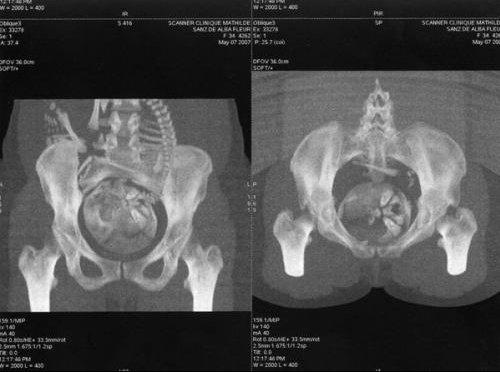

La radiopelvimétrie est une radiographie très précise (ou un sacnner) qui permet de mesurer au millimètre près les dimensions de votre bassin (« pelvis » en latin ») et de les comparer avec celles de la tête de votre futur bébé, de loin la partie la plus volumineuse de son corps Cet examen permet de savoir si votre bassin est suffisamment large pour laisser passer votre bébéLa radiopelvimétrie est une radio du bassin de la femme enceinte Par des clichés de face et de profil, elle fournit des indications concernant « la circonférence des axes du bassin de la mère » (selon la définition du professeur Frydman), ainsi que des indications concernant la position de la tête du bébé, celleci devant être fléchie avec le menton sur la poitrine Moi aussi pour mon 1er, j'ai eu une radio du bassin = pelvimétrie car le bébé était très haut et en siège J'ai une mesure trop étroite donc gynéco a décidé césarienne Ca s'est super bien passé et là, j'attends mon 2 pour fin aout et me parle d'une autre césarienne car cette foisci, le placenta est trop bas

La radio du bassin (radiopelvimétrie), pratiquée pour apprécier la forme et la dimension du bassin de la mère et évaluer les possibilités d'accouchement par lesAbsecon, NJ) ABN Automotive Broadcasting Network ABN Acronym Builders Network ABN Algemene Bank Nederland Pour mesurer la largeur de votre bassin, contrôler les différents passages osseux et avoir des indications précises sur le poids et la position de la tête de votre bébé, vous serez amenée à passer une radiopelvimétrie, radio du bassin, un scanner et/ou une échographie

Une radio du bassin est indiquée La HAS rappelle que cette radio du bassin doit être parfaitement réalisée pour être interprétable incidence de face, enfant immobilisé, réduction de la lordose lombaire et pieds en rotation interne Les radios du bassin ne sont pas indiquées initialement En revanche, des radios du rachis Les faces latérales du bassin sont explorées avec la main droite pour la face droite, la main gauche pour la face gauche L'arc antérieur est apprécié dans sa forme et son épaisseur, de même que l'ogive pubienne, la saillie des épines sciatiques, la mobilité de la pédale coccygienne Évaluer la courbure du sacrum et du coccyx Attendre le défilement des explications La radiopelvimétrie Cet examen, qui peut s'effectuer soit à l'aide de radiographies standard, soit à l'aide de coupes scanner, permet de mesurer les dimensions du bassin osseux et de voir si un accouchement par voie basse est théoriquement possible

j'ai passé un scanner du bassin environ 1 mois avant d'accoucher je te rassure ça ne fait pas mal, tu ne sens rien et on ne t'injecte pas de produit tu ne vois pas du tout le bébé il mesure les os de ton bassin pour voir si le passage est assez large pour l'accouchement voilà pour mon expérience vas y sans crainte c'est fait en 2 min biz'radiographie hanche et bassin ccam radiologie april 26th, radiographie de la ceinture pelvienne du bassin selon 1 in et unilat coxofémorale selon 1 ou 2 in naqk071 si tu fais 3 incidences ou plus sur la hanche tu sorts de ce cadre et tu peux coter un bassin associé avec une hanche voir liste dans ce lien radio appareil looteur Peut on voir un bb sur une radio du bassin ?